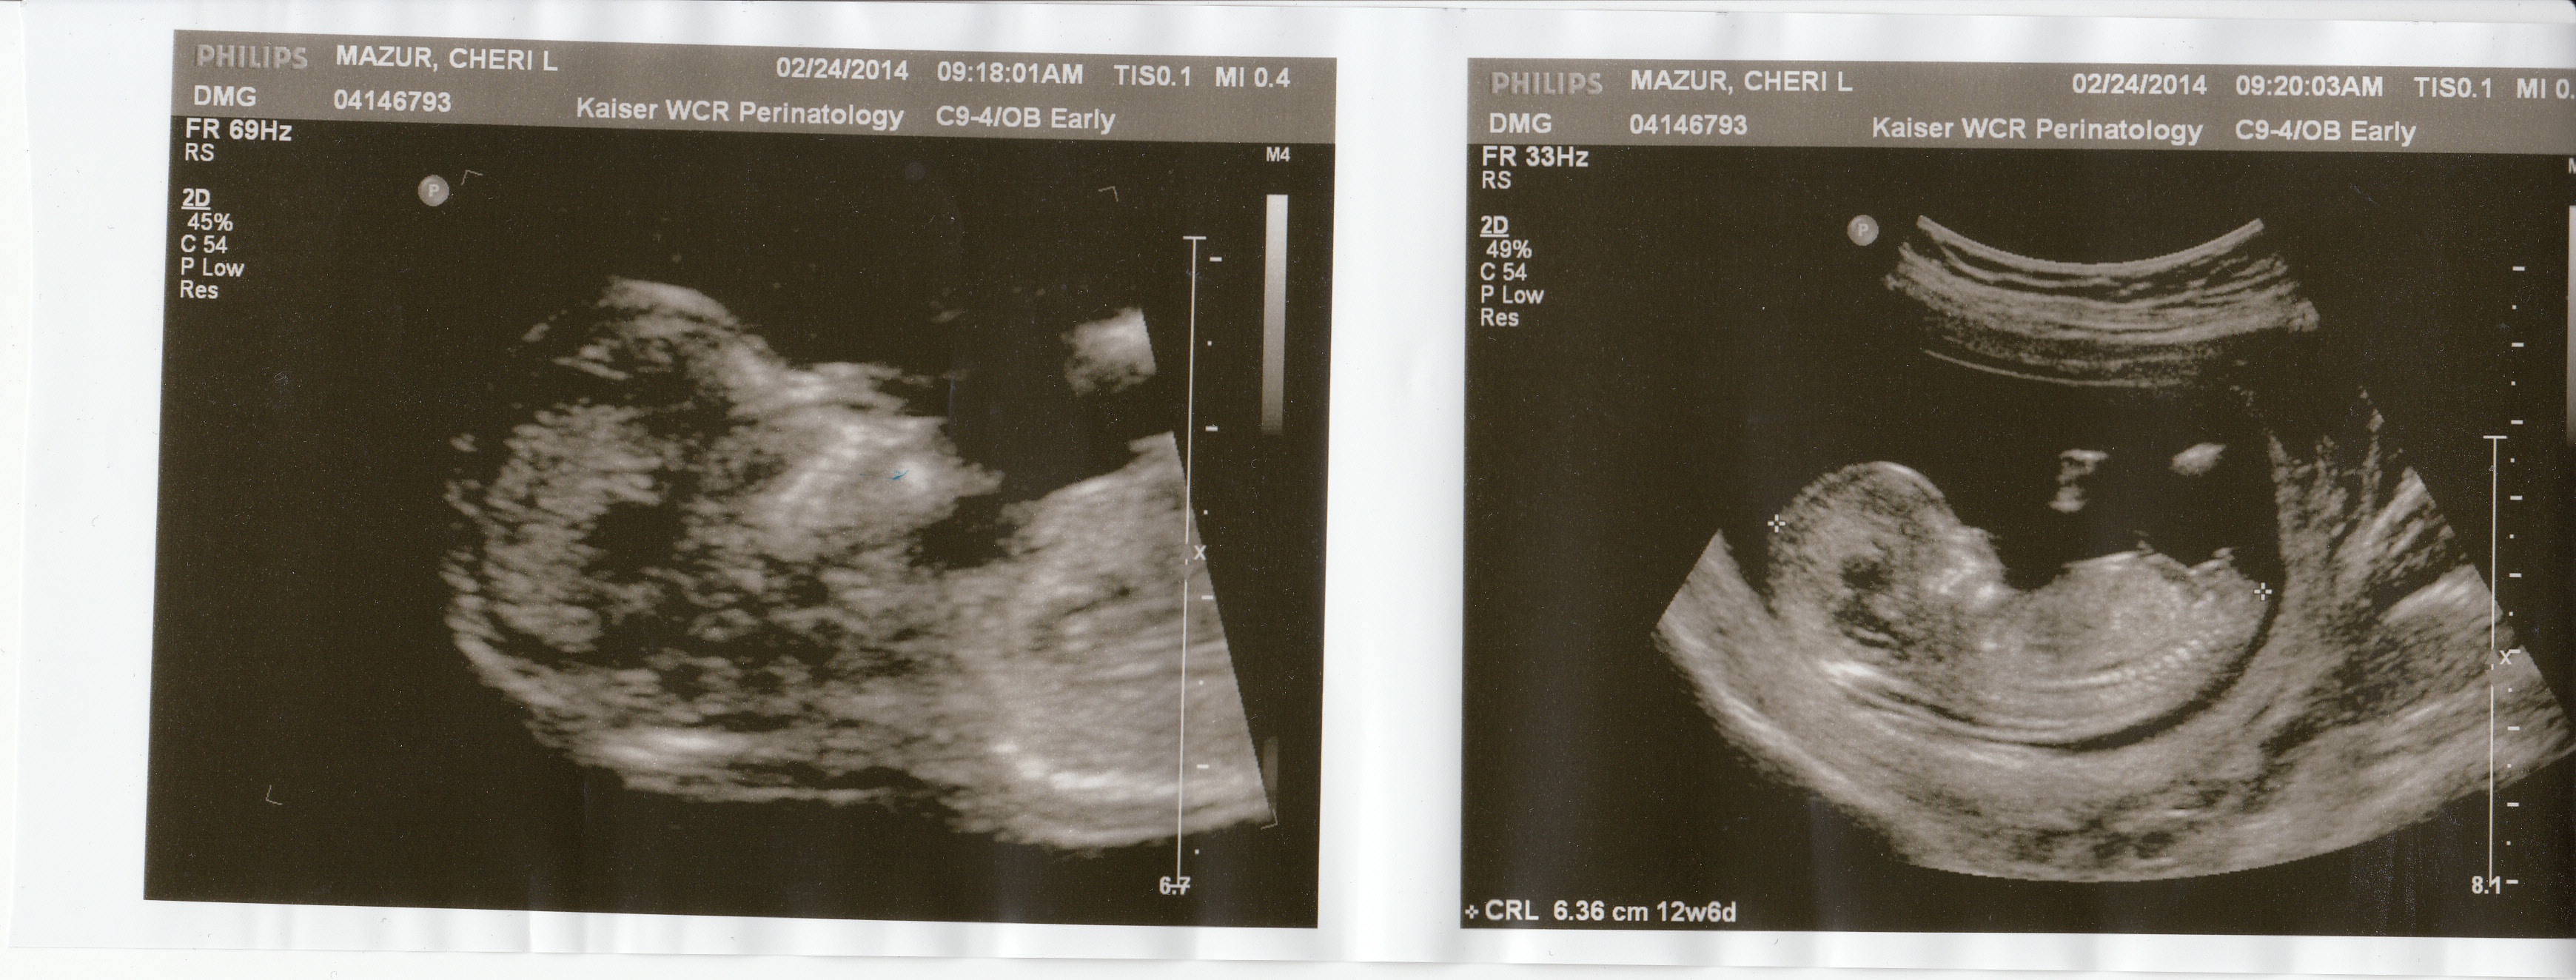

I am unsure what a two dot theory is for boys...I know the three line thing for girls. Also how do I know what side my placenta is? thanks so much for the help :) I have attache ultrasound pics just in caseAttachment 18028

I'm pretty sure that's a boy nub:)

Very boyish nub xx